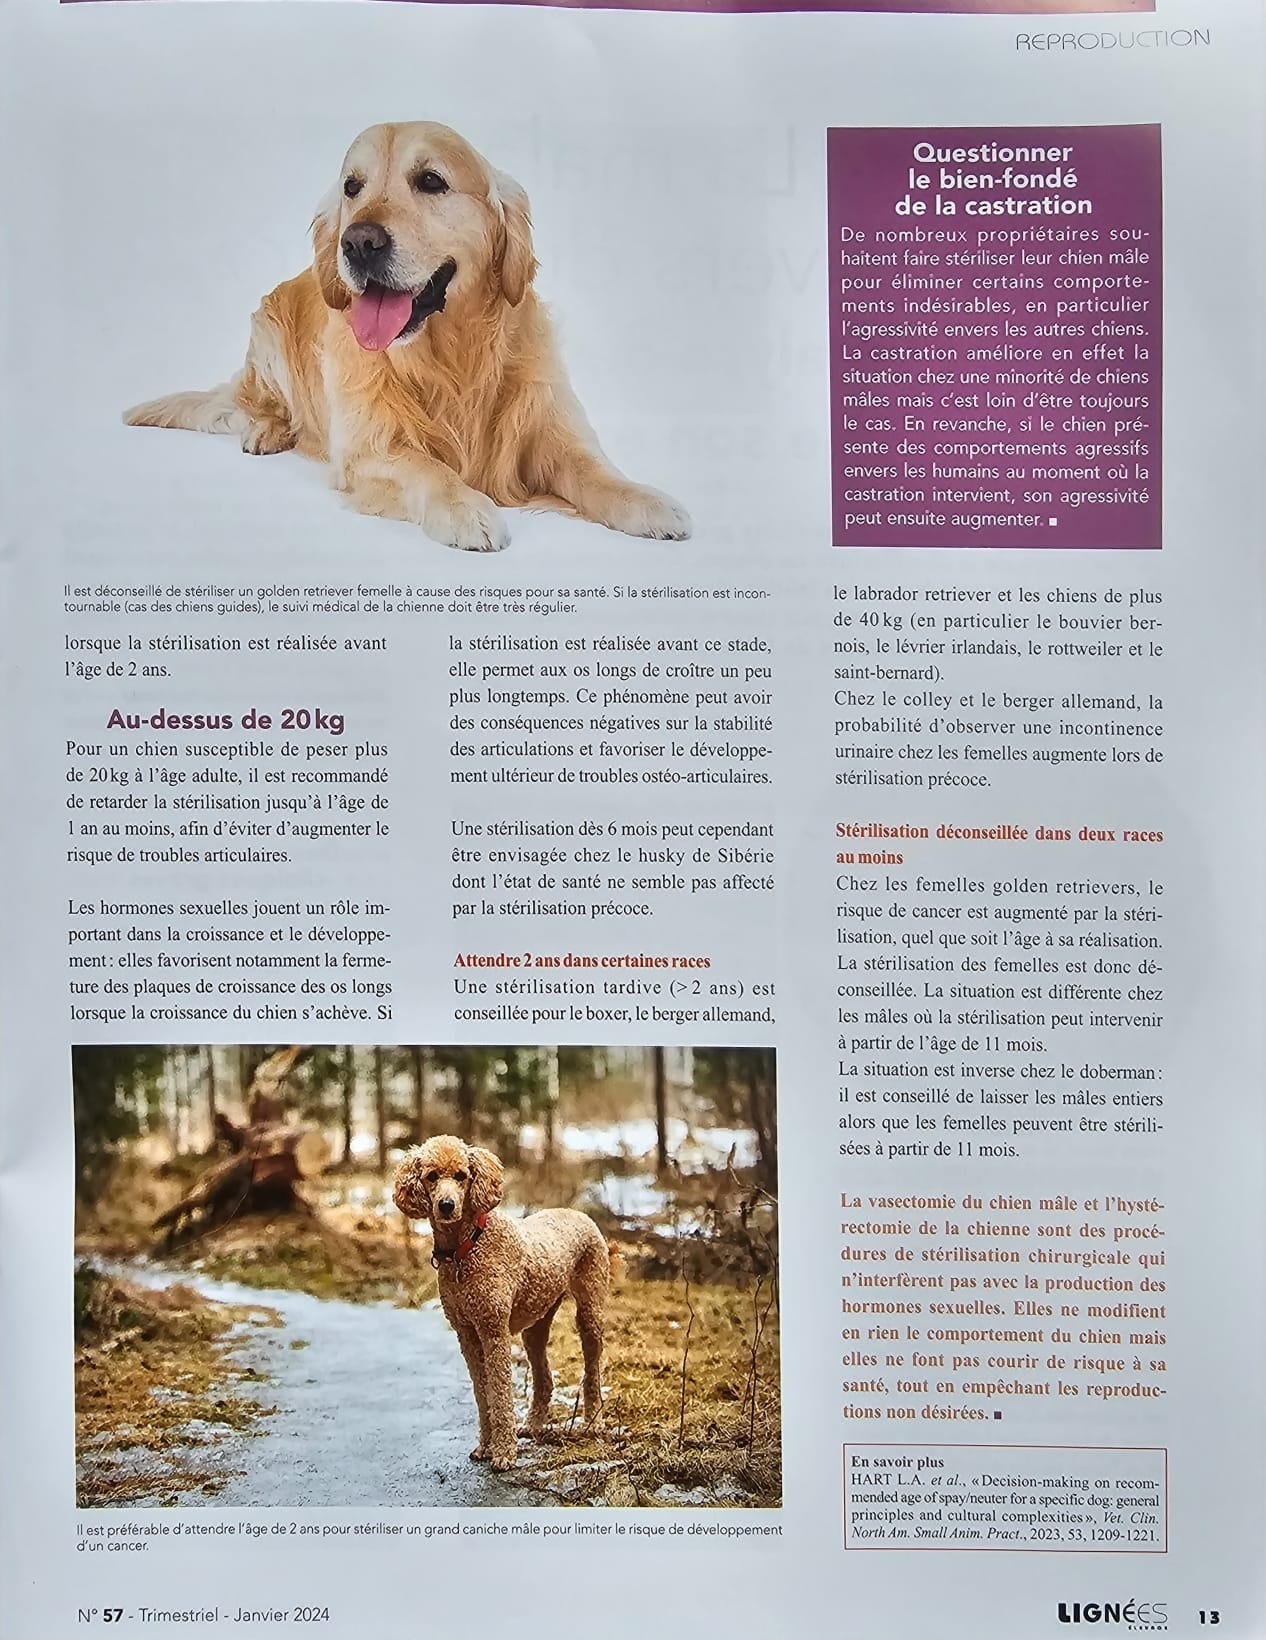

Age à la stérilisation selon les races

Article du magasine Lignées spécial élevage

Age à la stérilisation selon les races

Article du magasine Lignées spécial élevage